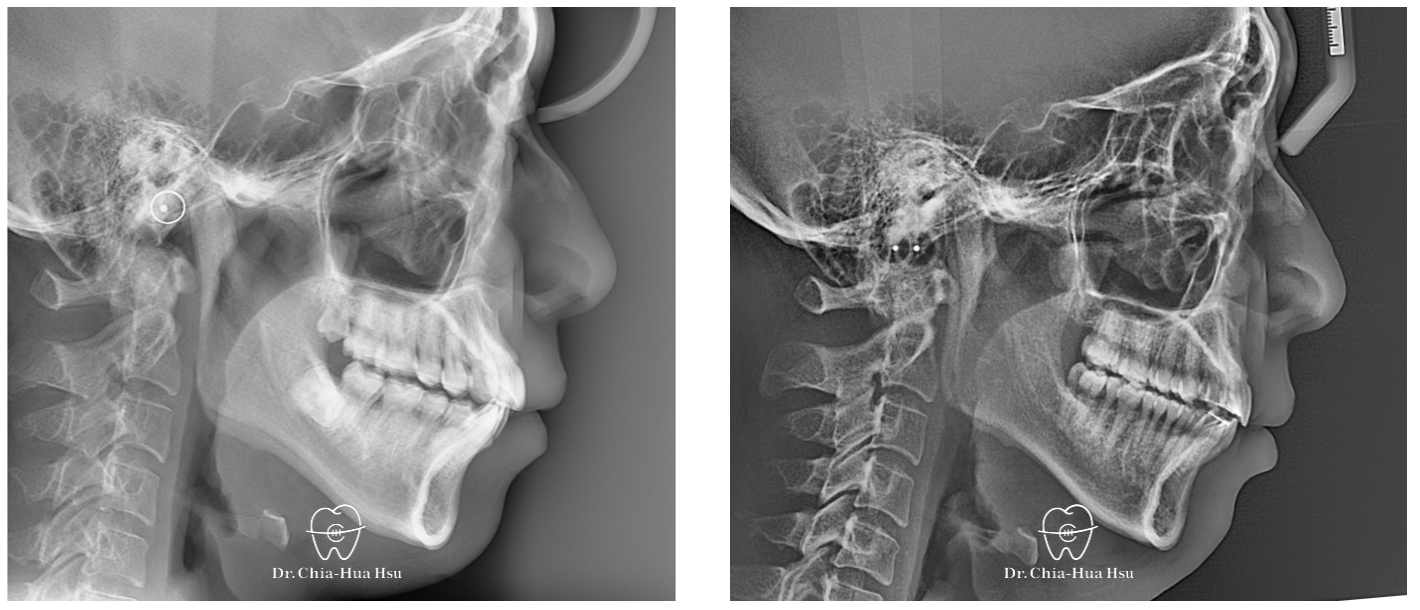

• 問題分析:患者是標準的骨骼一類咬合(Skeletal Class I)伴隨齒列擁擠以及嘴唇微凸,初診時口內有許多牙結石與牙齦紅腫發炎的問題。

治療前

治療後